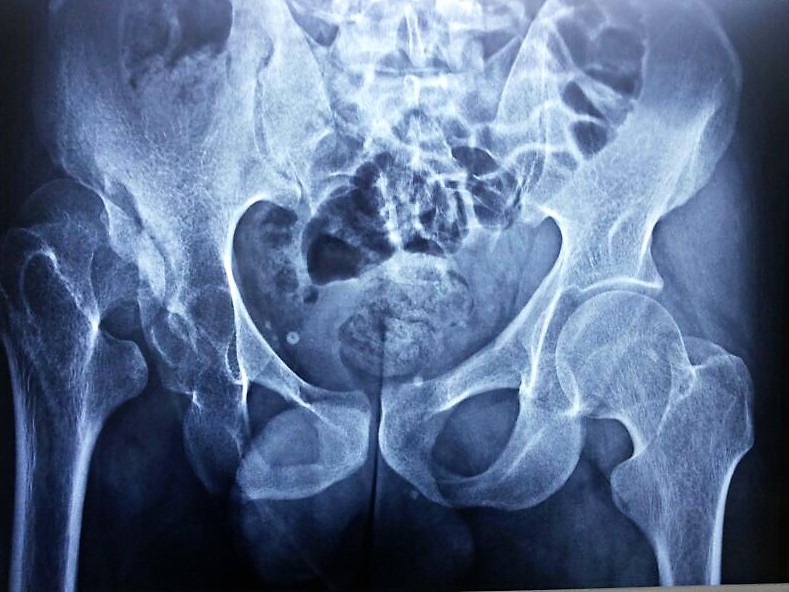

حالات ما بعد العمليات الجراحيه للعمود الفقري والمفاصل |

هشاشة العظام |

تشوهات العظام |